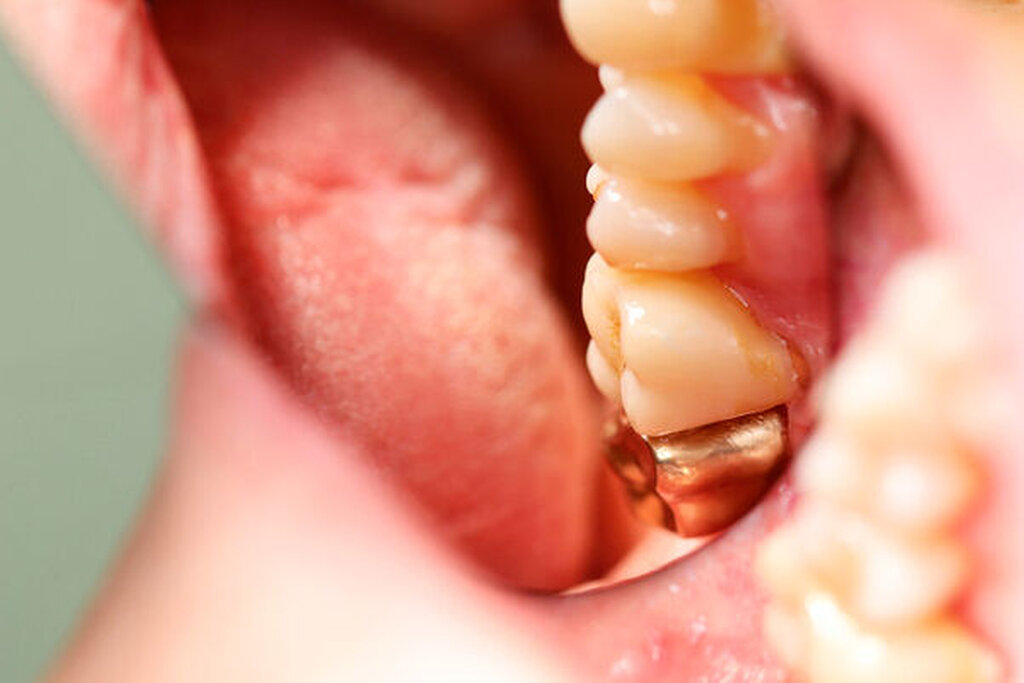

Nach der Wurzelamputation erfolgte in allen hier dargestellten Fällen nach etwa vier Wochen Ausheilzeit die prothetische Versorgung der Zähne mit Einzelkronen.

Im Rahmen der Versorgung erfolgte auch ein Austausch der Extensionsbrücke 16–14 durch Einzelkronen auf 16 und 15 sowie einer Implantatversorgung mit Einzelkrone in Regio 014. Der Erhalt des Zahnes 16 ermöglichte so eine wenig invasive Versorgung des ersten Quadranten mit guter Hygienefähigkeit. Alternativ wäre bei Extraktion des Zahnes die Versorgung beispielsweise mit einer ausgedehnten Brückenkonstruktion von 13–17 oder einem weiteren Implantat in Regio 016, vermutlich mit (indirektem) Sinuslift, notwendig gewesen. So konnte der Fall minimalinvasiv zufriedenstellend gelöst werden. Die Patientin ist seit dem Eingriff beschwerdefrei und kommt gut zurecht. Die Situation ist nun seit sechs Jahren stabil.

Darauf erfolgte die Amputation der palatinalen Wurzel mit anschließender Versorgung durch eine vollkeramische Krone. Die Situation ist nach inzwischen drei Jahren weiterhin stabil, die Patientin kommt mit der Versorgung gut zurecht, lediglich palatinal finden sich leicht erhöhte Sondierungstiefen.

So erfolgte die Amputation der distobukkalen Wurzel mit anschließender Versorgung des Zahnes mittels Vollkrone. Die Situation an 16 ist seitdem für den Patienten subjektiv stabil, die aktuelle Röntgenkontrolle zeigt jedoch eine Progredienz der parodontalen Defekte trotz regelmäßiger UPT und subjektiv guter Mitarbeit des Patienten, was die Prognose des Zahnes negativ beeinflusst. Ursächlich hierfür kann eine persistierende parodontale Infektion durch den trotz Wurzelamputation immer noch schwer für die häusliche Mundhygiene zugänglichen Furkationsbereich mit enger Lagebeziehung der mesiobukkalen und der palatinalen Wurzel sein. Der Patient ist allerdings aktuell mit der Situation zufrieden und beschwerdefrei und wünscht daher noch keine Extraktion des Zahnes, auch wenn diese sich nun fünf Jahre nach dem initialen Befund nicht mehr sehr lange vermeiden lassen wird.

So folgte nach der Wurzelfüllung die Amputation der mesiobukkalen Wurzel. Der Zahn wurde nach der Amputation auf Wunsch der Patientin zunächst mit einem Langzeitprovisorium versorgt, das im Verlauf gegen eine definitive Versorgung ausgewechselt wurde. Die Patientin ist seitdem an 16 beschwerdefrei, der Zahn ist stabil und hat eine gute Langzeitprognose.